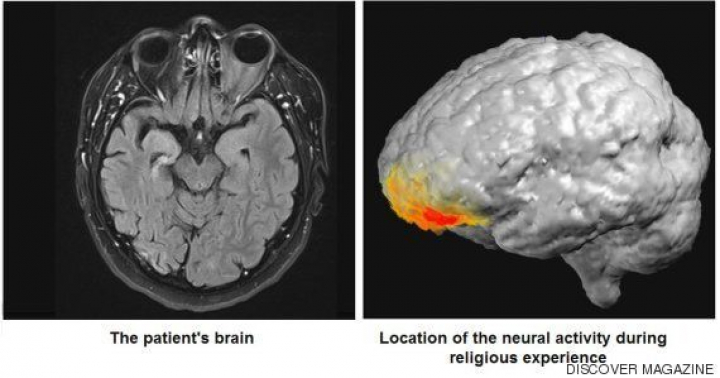

Tal vez alguna respuesta sobre cómo se producen las alucinaciones pueda llegar gracias a un estudio publicado ahora que, por una afortunada casualidad, ha permitido observar el cerebro de un hombre justo en el momento en que experimentaba un potente delirio en forma de revelación mesiánica. Sucedió en el Centro Médico Hadassah de la Universidad Hebrea de Jerusalén. El paciente era un hombre de 45 años, judío pero sin especial devoción religiosa, y que desde niño sufría una epilepsia del lóbulo temporal para la que había sido medicado en varias ocasiones.

Tras el examen psiquiátrico, el paciente fue diagnosticado de psicosis postictal (PPI), un cuadro de alteraciones que aparece en ocasiones tras una crisis convulsiva, cuando el cerebro se está recuperando, y que puede incluir alucinaciones. "Se han documentado numerosas experiencias religiosas en pacientes con epilepsia, aunque el mecanismo neural exacto que las provoca aún no está claro", escriben Arzy y Schurr.

Analizando los datos grabados, los investigadores descubrieron que el delirio religioso se correspondía con una hiperactividad del córtex prefrontal izquierdo del cerebro del paciente, lejos de su lóbulo temporal donde se originaban las crisis epilépticas. Durante la visión mesiánica, esa región generaba un tipo de ondas llamadas gamma, que suelen asociarse a la atención consciente y que, curiosamente, se han registrado en monjes tibetanos durante la meditación.